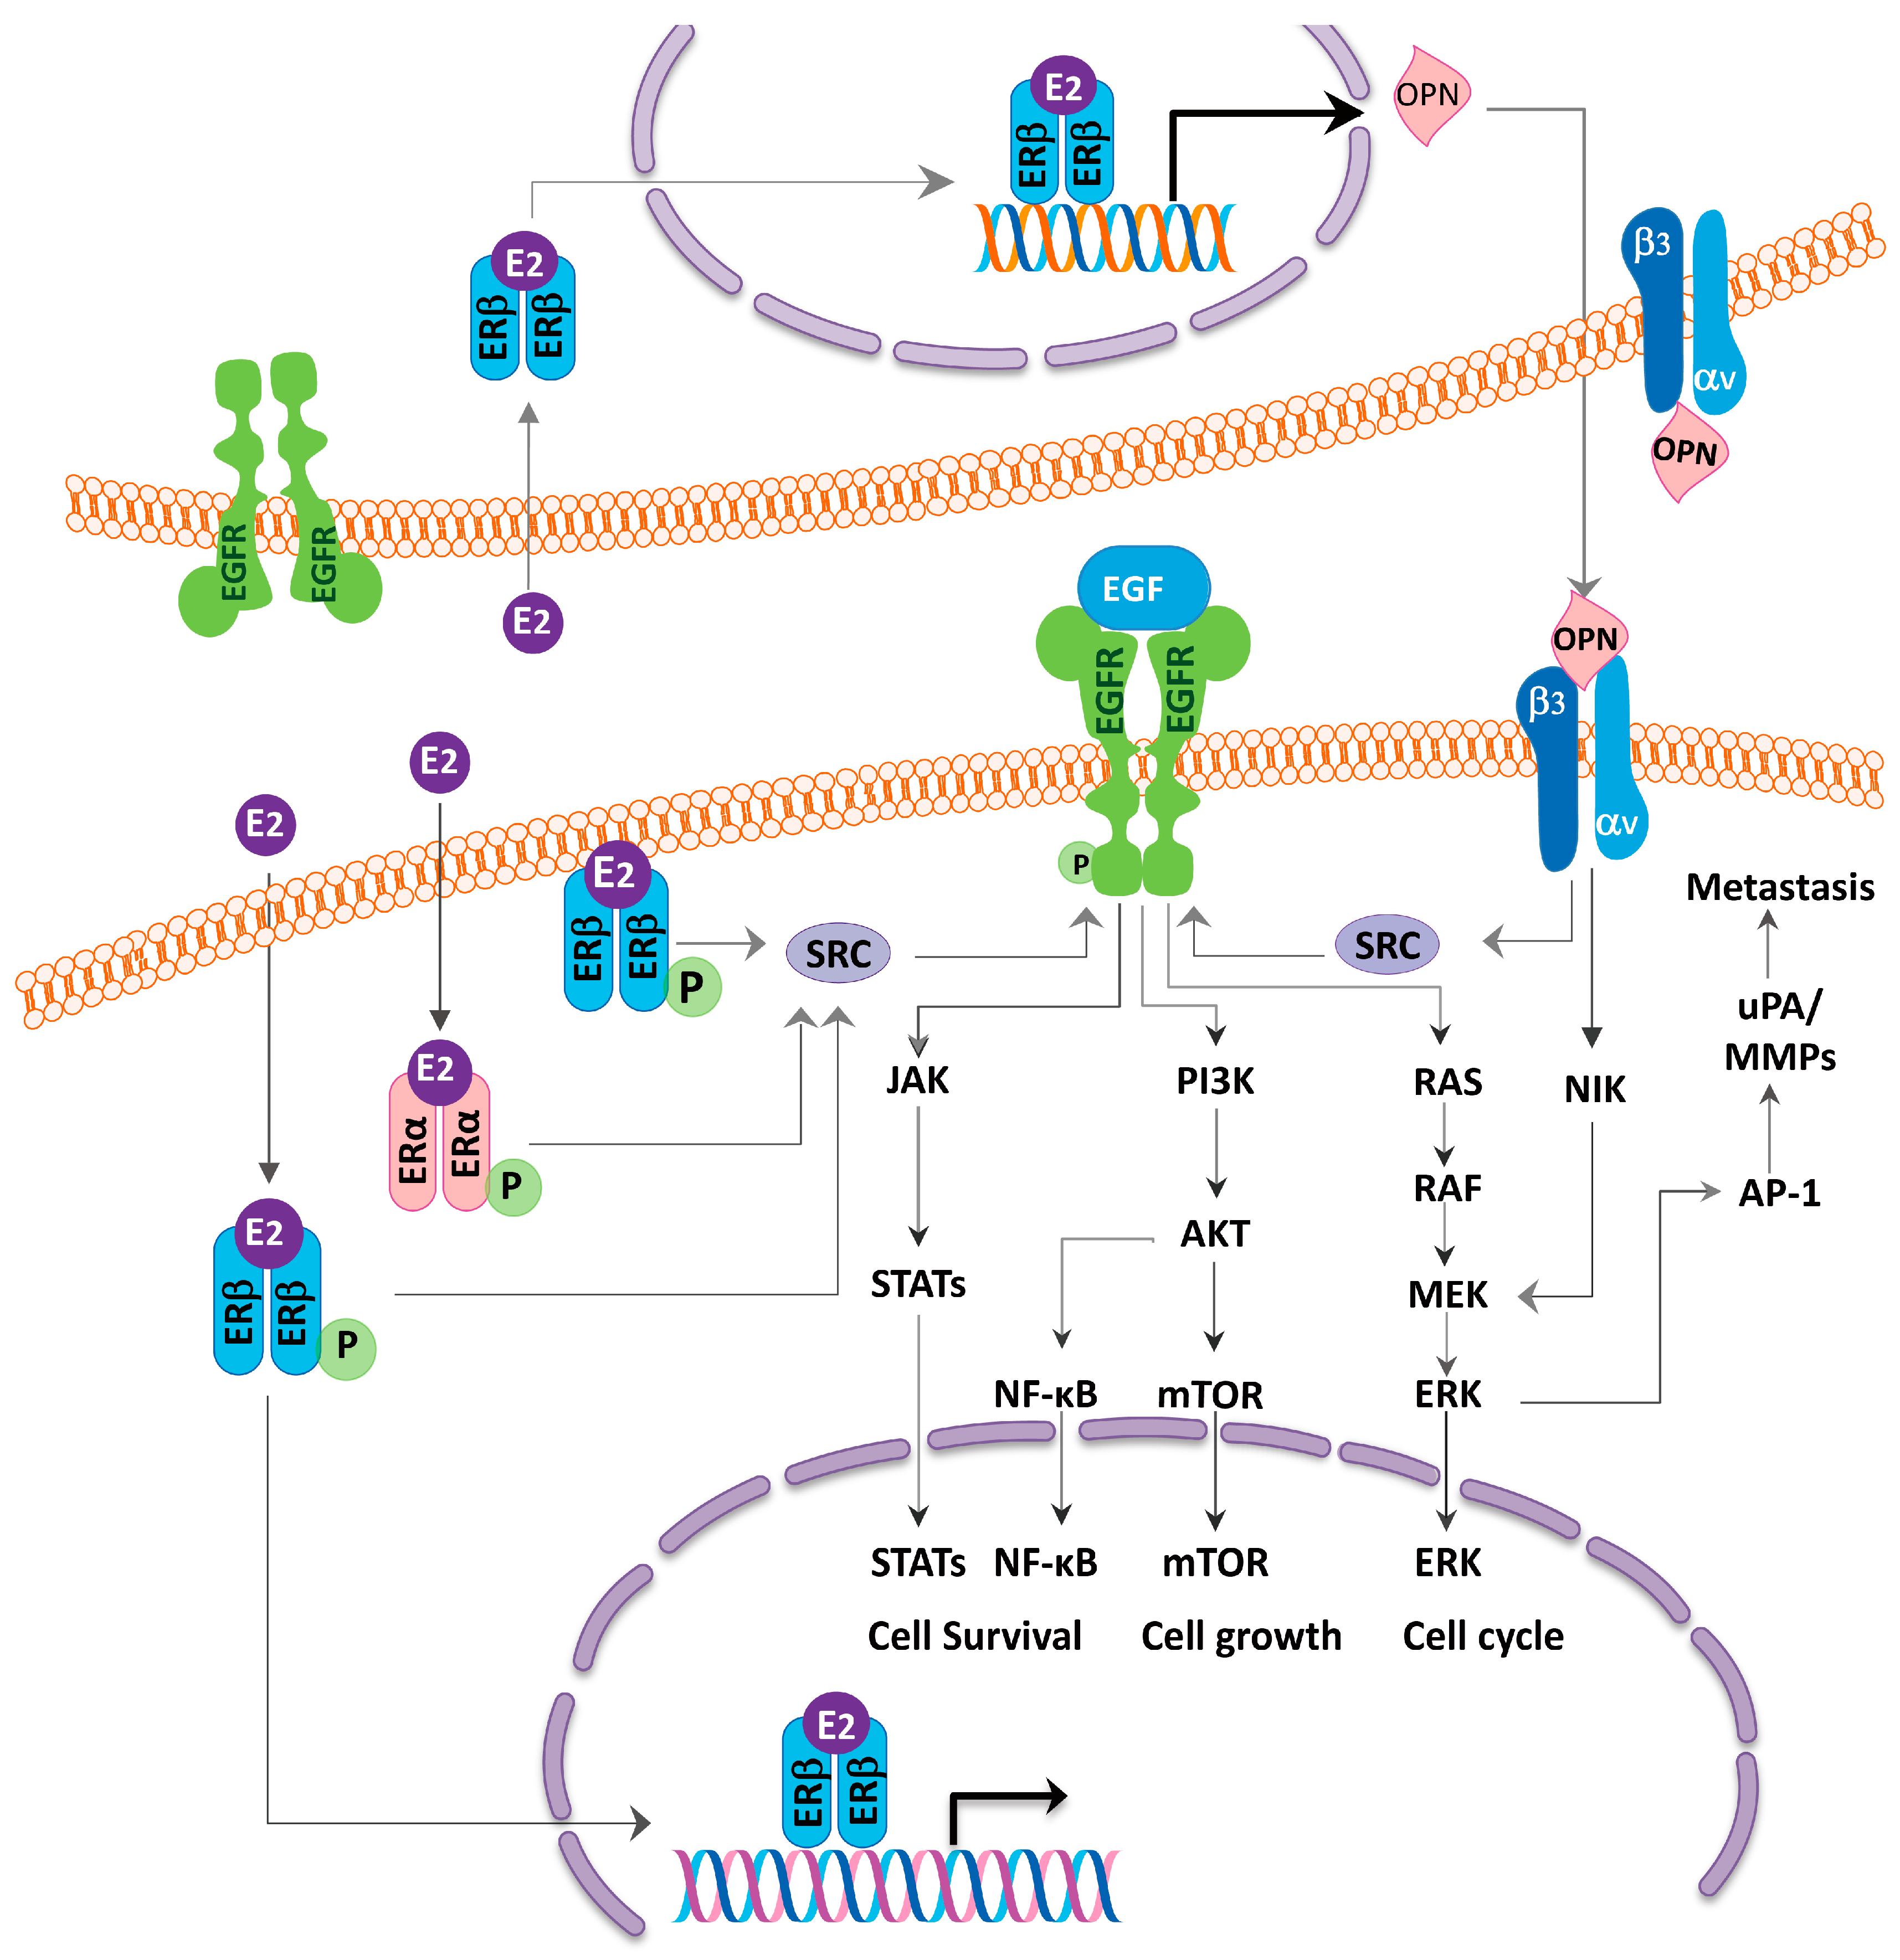

4. ER as Targets for Lung Cancer Therapy and Relationship with EGFR